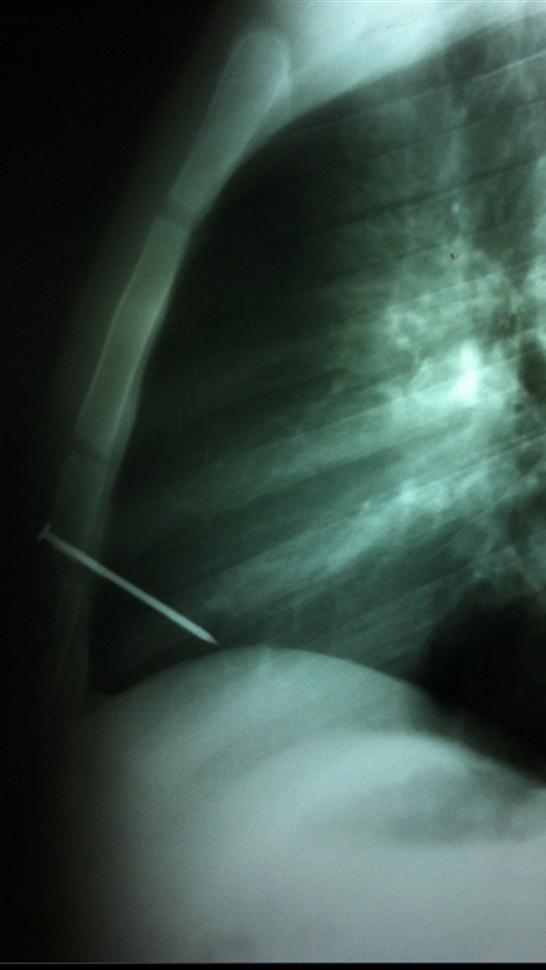

BUENOS AIRES.- Un joven de 19 años estuvo al borde de la muerte y se escapó. El lunes, recibió el disparo de una pistola neumática que manipulaba un compañero, que provocó que se le incruste un clavo en el corazón, por lo que fue intervenido de urgencia. Un equipo médico del hospital El Cruce Néstor Kirchner, de la localidad bonaerense de Florencio Varela fue el responsable de la operación que convirtió al joven en la cuarta persona en el mundo en sobrevivir a esta cirugía.

El clavo, de ocho centímetros de largo, había atravesado el esternón y el ventrículo derecho del corazón, y quedó alojado en la cavidad cardíaca. (Télam - DYN)

"En el quirófano se procedió a la apertura del hueso del esternón con mucho cuidado porque se corría el riesgo de chocar con el clavo y agrandar la herida cardíaca", explicó el médico Marcelo Nahín, quien dirigió la cirugía. "Ya con el elemento perforante a la vista realizamos la extracción manual del objeto que se había incrustado en la cara anterior del ventrículo derecho", detalló.